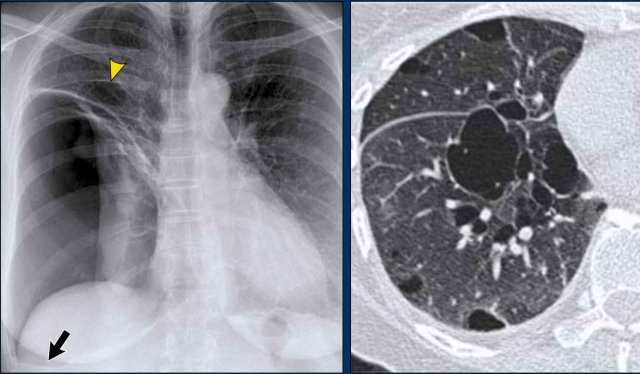

On the PA chest radiograph, a lateral displacement of the azygoesophageal line can be seen.

It is caused by a hiatal hernia.

The arrow points to the barium contrast within the hiatal hernia.

Displacement of the Azygoesophageal Line (1) – Hiatal hernia

A hiatal hernia (arrowheads) is the most common cause of displacement of the azygoesophageal line as seen on the PA-view.

Notice the air within the hernia on the lateral view (black arrow).